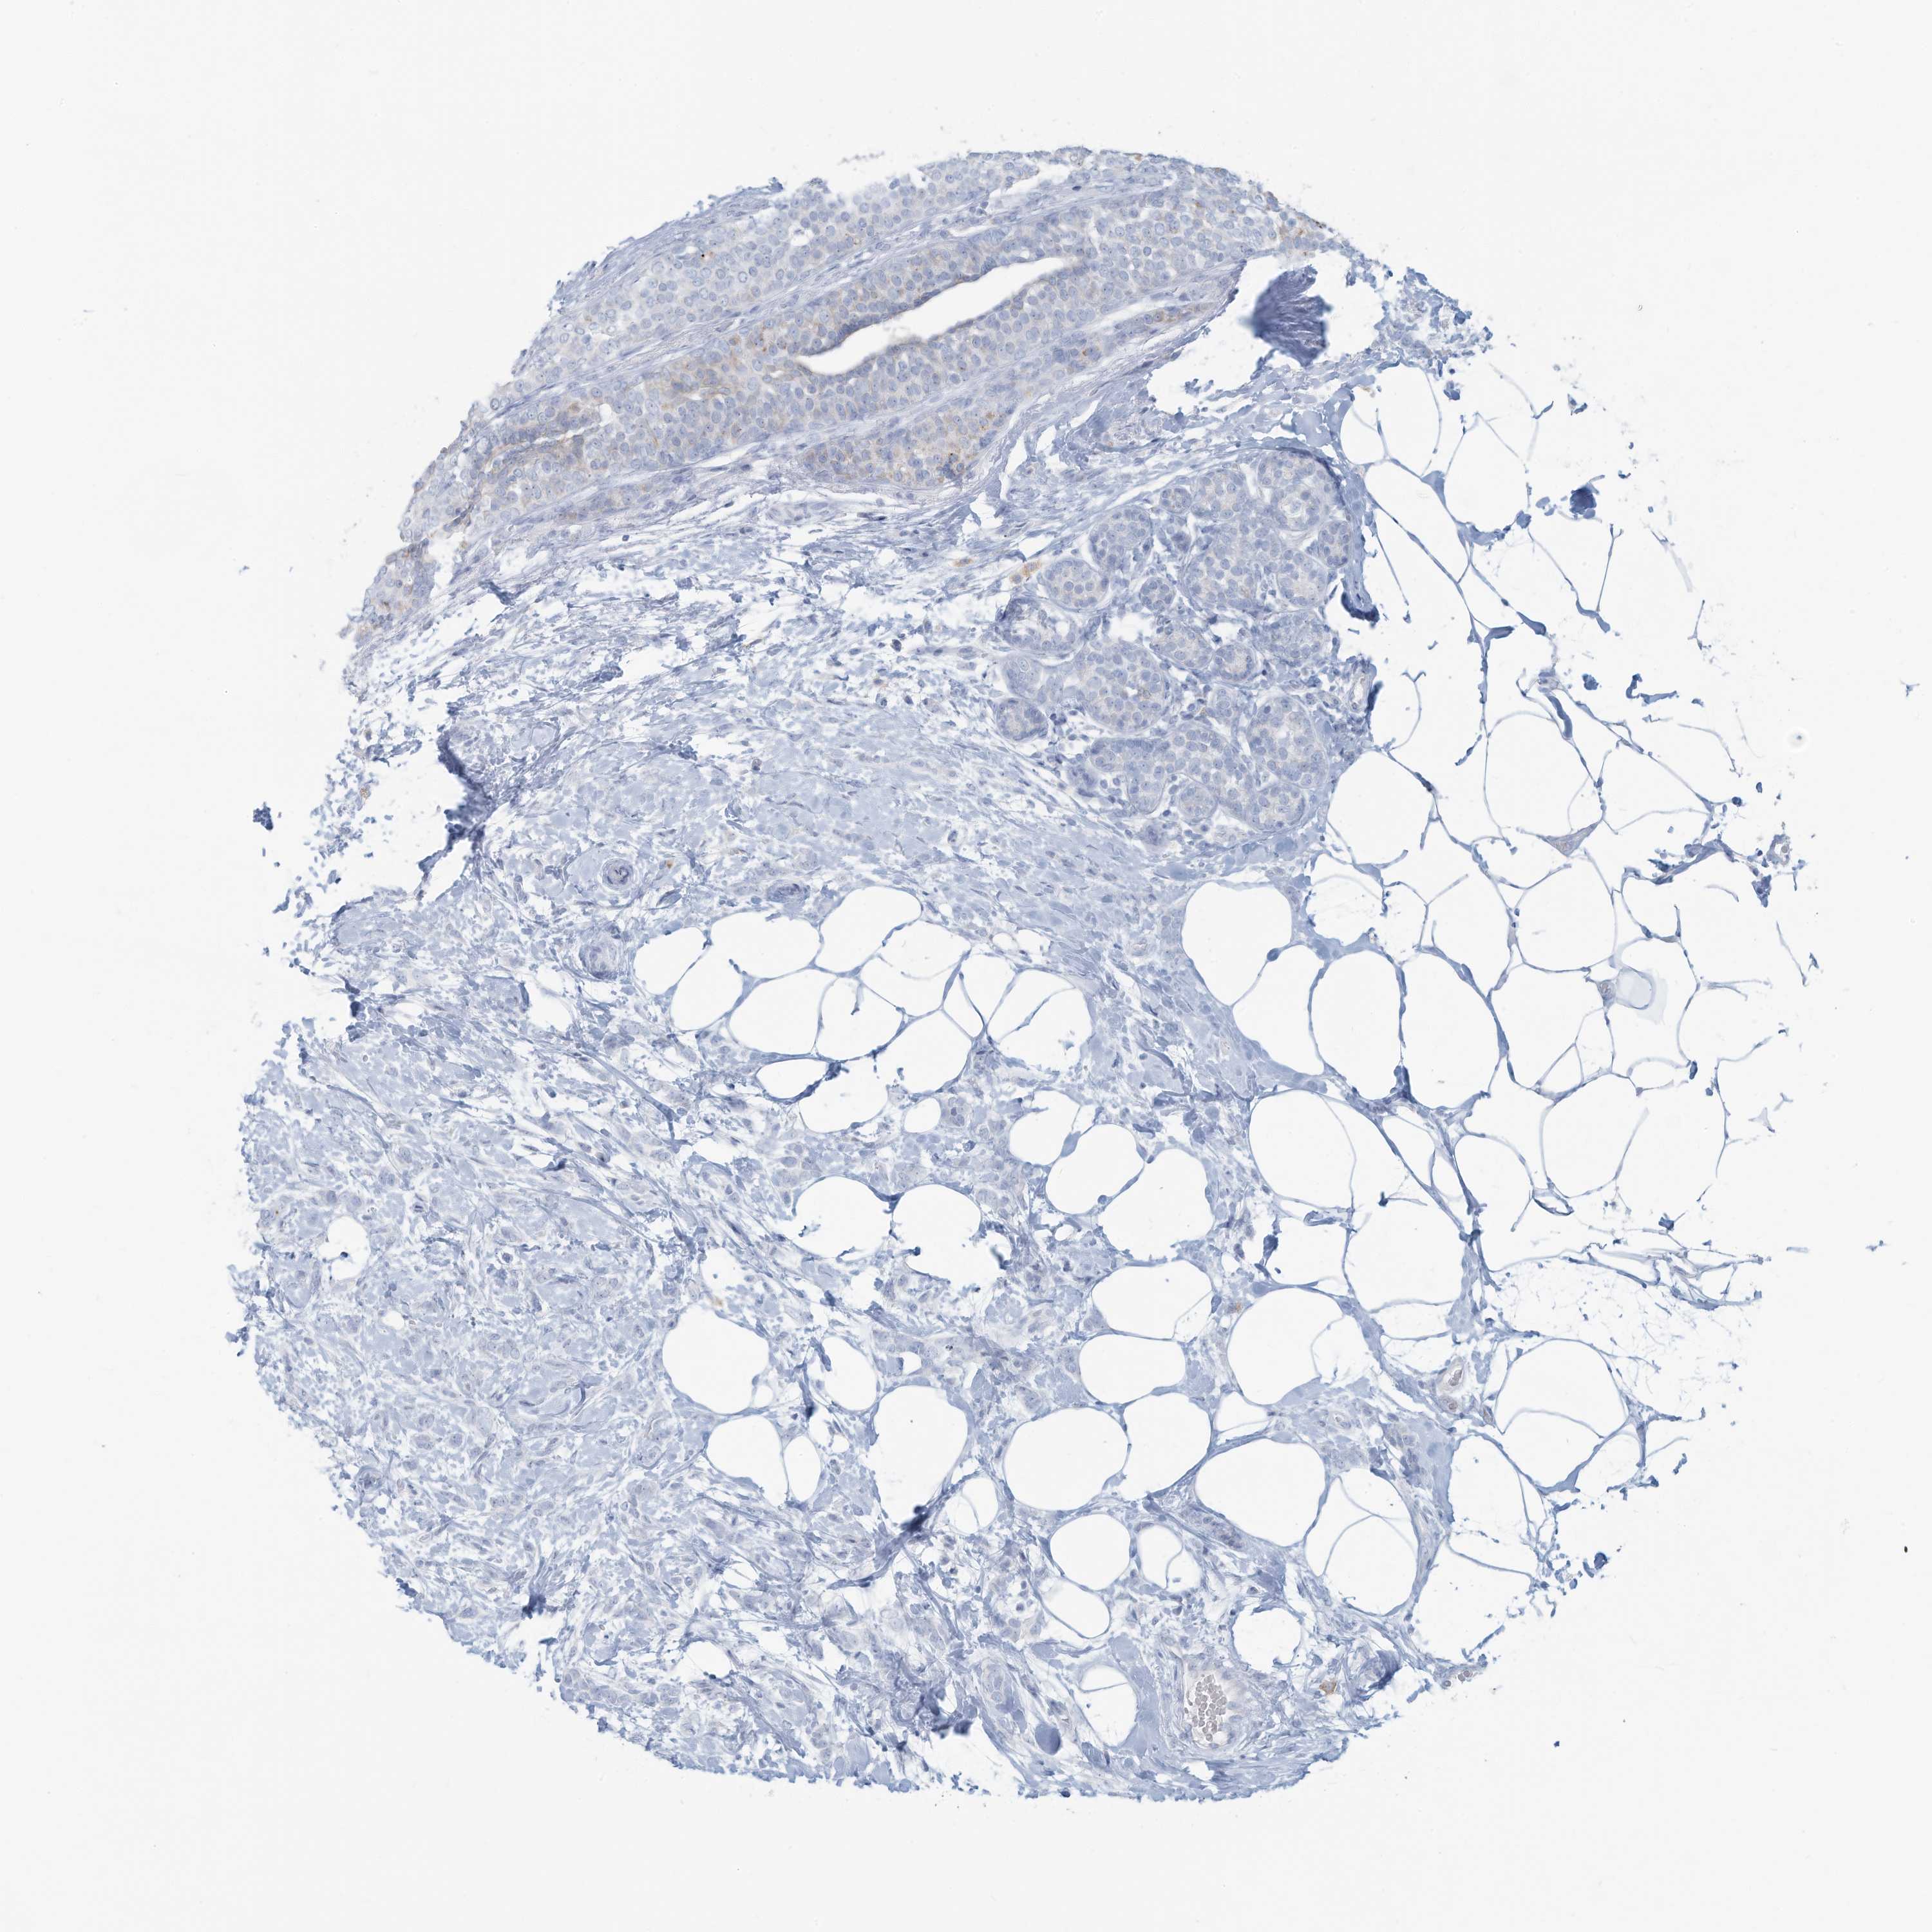

BRCA TCGA BRCA VALIDATION PROTEIN EXPRESSION

ANTIBODIES

AND

VALIDATION